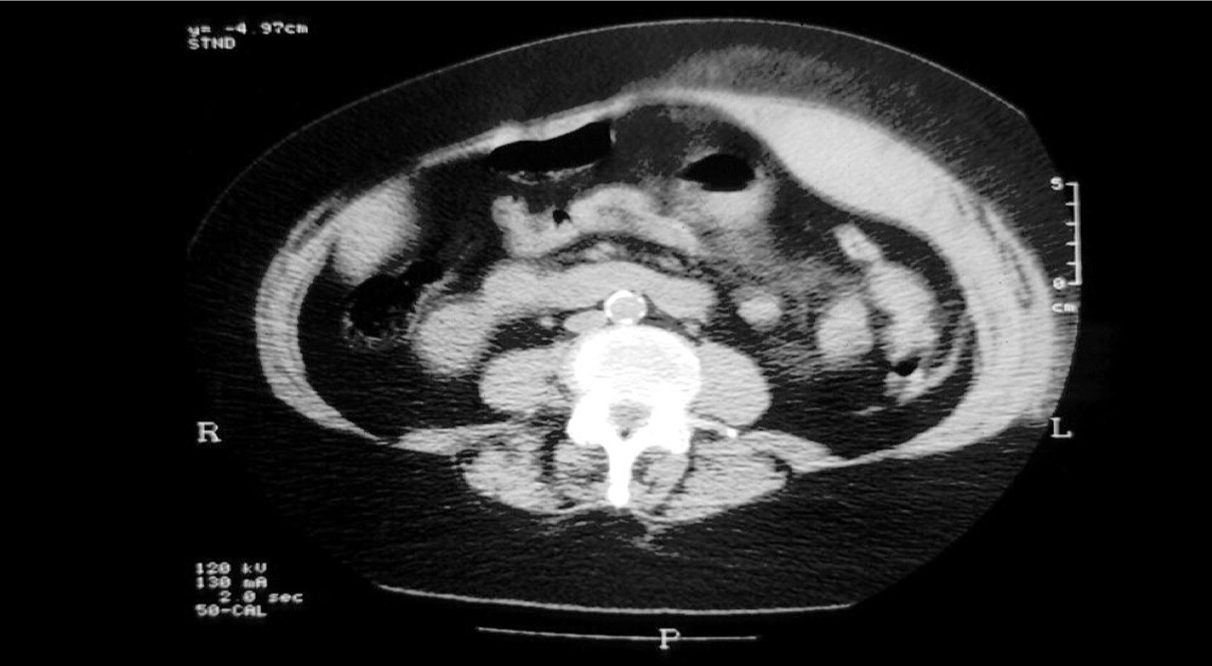

what is shown here?

Rectus Sheath Haematoma